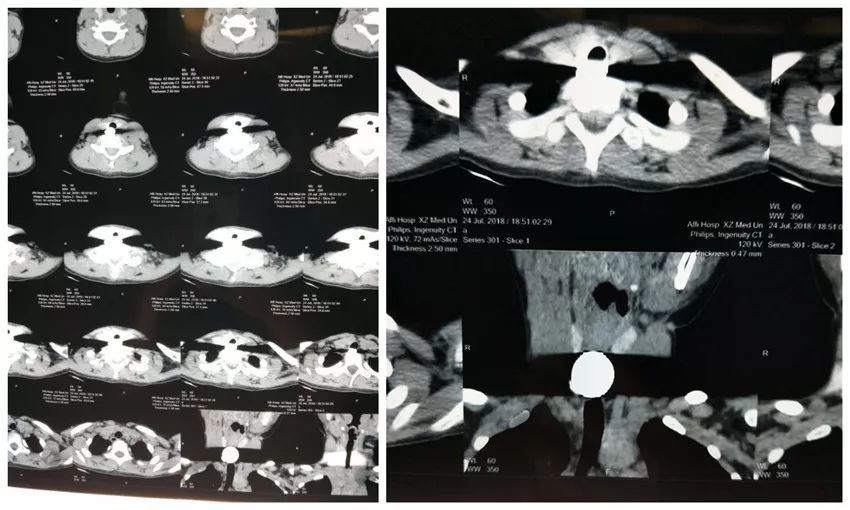

9歲女童誤吞2枚硬幣:卡在食道,無(wú)法吞咽昨天下午,9歲的琪琪和7歲的弟弟在家中玩耍,從外面買菜回來(lái)的奶奶就順手把找零的4元硬幣交給琪琪,讓她放到存錢罐中,然后就去廚房準(zhǔn)備做晚飯。大約半小時(shí)后,弟弟突然著急地跑到廚房告訴奶奶:姐姐把2枚硬幣放在嘴里,結(jié)果坐在地上仰頭看電視居然吃下去了!奶奶聽(tīng)到后嚇得腿都軟了,這時(shí)兩姐弟的父母下班回來(lái),知道琪琪誤吞了2枚硬幣后立即將她送到當(dāng)?shù)蒯t(yī)院,CT片顯示食道上段異物,考慮到琪琪誤吞了2枚硬幣,醫(yī)生建議轉(zhuǎn)院治療。

接診時(shí),徐州市礦山醫(yī)院眼耳鼻喉科醫(yī)生發(fā)現(xiàn),琪琪出現(xiàn)惡心嘔吐現(xiàn)象,并伴有胸前區(qū)疼痛,拒絕進(jìn)食。這時(shí),琪琪已吞下硬幣4個(gè)小時(shí),又餓又累,說(shuō)不出話來(lái)。

“卡在食道,無(wú)法吞咽!”當(dāng)晚,眼耳鼻喉科袁麗娟主任從家里匆忙趕來(lái),查看相關(guān)檢查結(jié)果后決定立即為琪琪進(jìn)行手術(shù)。在麻醉科配合下為其全身麻醉,食道鏡導(dǎo)入,在食道入口處下5CM處即見(jiàn)灰白色硬幣樣異物組織,予異物鉗同時(shí)夾住,取出,手術(shù)歷時(shí)5分鐘。